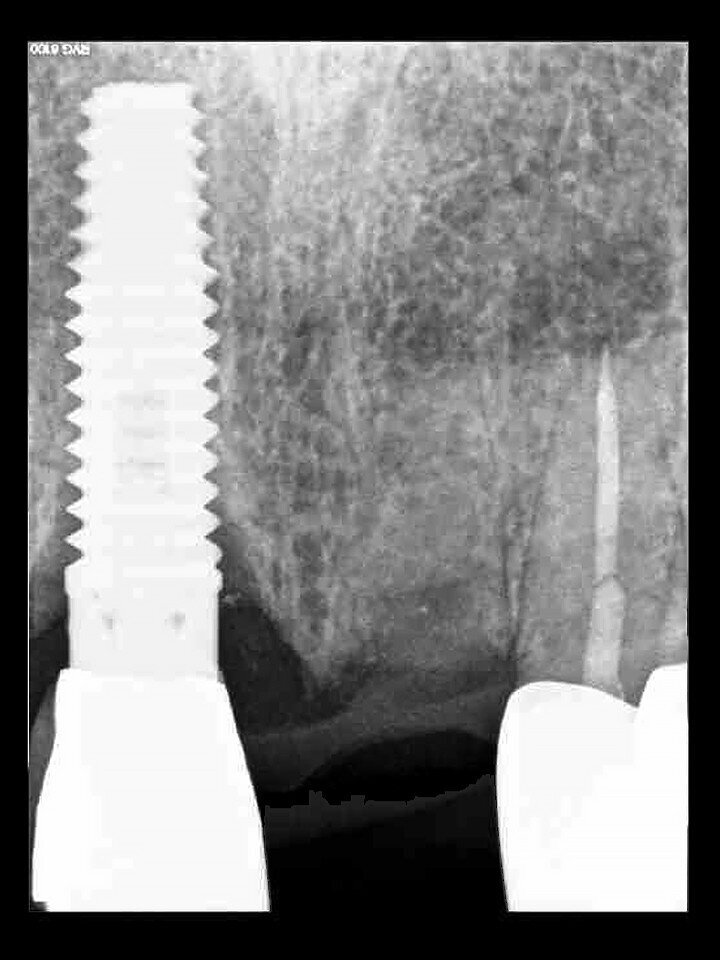

Fig. 18: A periapical radiograph

with a drill in place confirmed that the apex length had been reached and that all the gutta-percha had been removed.

Prior to the guided drilling, a Gates–Glidden drill was used to remove any gutta-percha within the root. Utilising the tooth-borne template and the first insert, initial long shaper drills (IS1, IS2) were used to reach the apex of the root (Root Membrane Kit; Fig. 17). A periapical radiograph confirmed that the apex length had been reached and that all the gutta-percha had been removed (Fig. 18). The second insert had a metal cylinder that allowed for the long, round diamond drills to shape the root into the desired crescent shape (Fig. 19a). The insert was removed to access the palatal root (Fig. 19b). Using appropriate instrumentation such as periotomes, elvatomes or FRINGS forceps (both TBS Dental), the palatal root was carefully removed (Fig. 20). A periapical radiograph confirmed that the palatal root had been completely removed (Fig. 21). The next insert contained the final diameter to receive the guided sleeveless drills for osteotomy preparation (Fig. 22a). The osteotomy was prepared to avoid proximity to the remaining root fragment while leaving sufficient restorative space, as previously planned in the software simulation (Fig. 22b). Implant placement (AnyRidge, MegaGen) was facilitated by the R2GATE surgical carrier for full-template guidance at the appropriate torque values (Fig. 23). Depth control and rotational positioning were accurately confirmed with the notch indicated on the template to correspond with the insertion tool (Fig. 24).